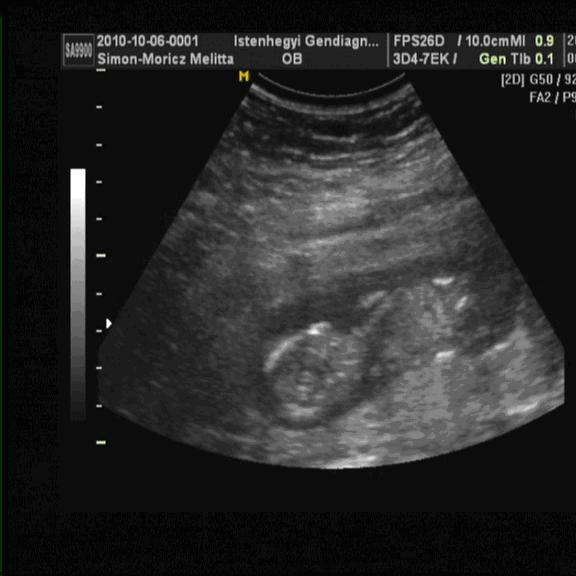

Akkor végre a két magzatunk sorrendben.

Kép A baba

Kép B baba

momelcsi

Melcsi, húúú nagyon cukik és milyen jól látszanak :lol: 4Ds ultrahangra is mentek majd? Neveitek már vannak vagy csak akkor döntitek el,ha megtudjátok a nemüket?